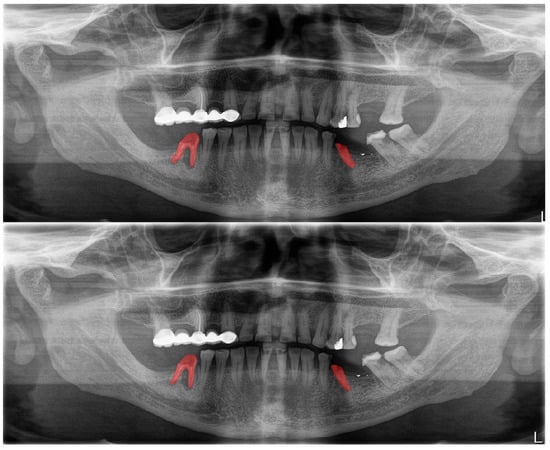

Figure 7.

Automatic segmentation of residual roots. Manual segmentation (upper image) and automatic segmentation (lower image) can be seen above.